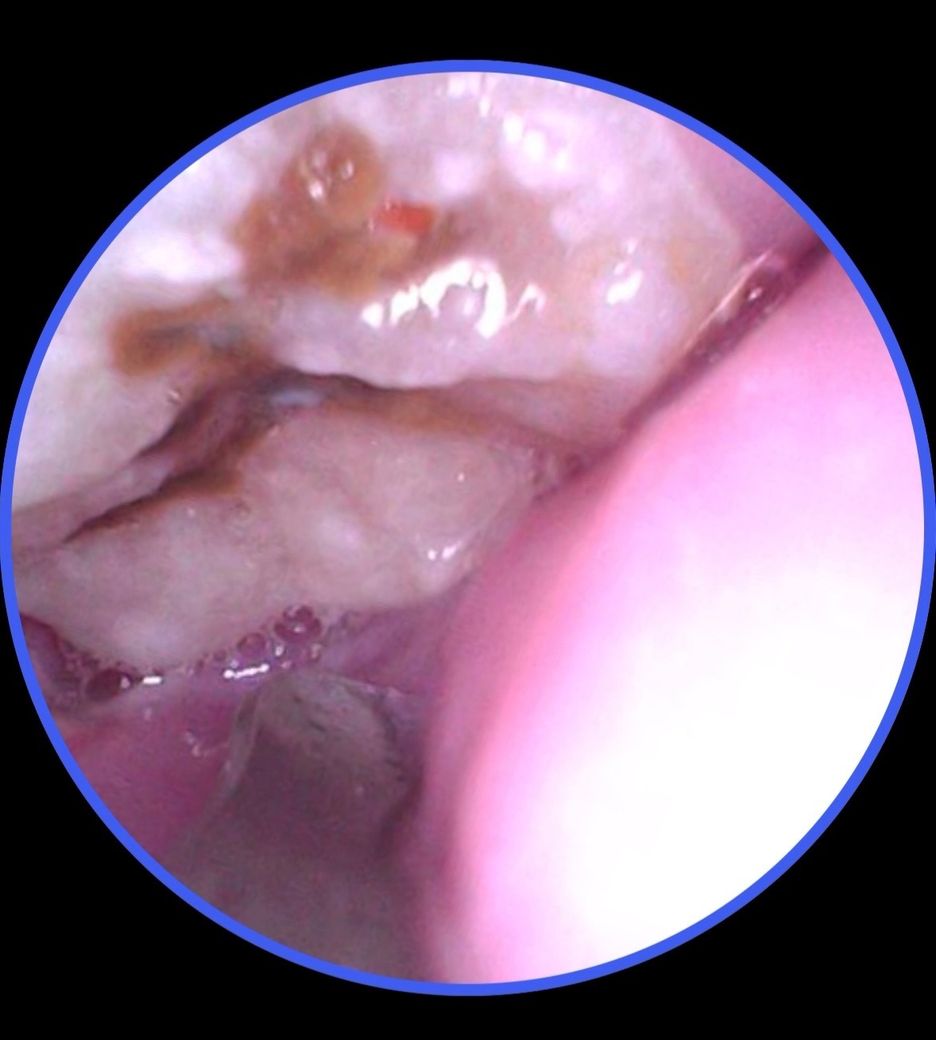

+추가로 한쪽에는 치아에 붉은 점 같은게 있는데 음식물은 아닙니다. 이건 뭔지도 문의 드립니다.

• 2번 째 사진

충치가 잇는거 같으니 발치를 하시는게 좋을것같고 치아 깨진부위에 음시굼ㄹ이 껴 잇는게 아닐까 싶습니다.

최근 내시경으로 확인 후 심하게 갈색으로 변색되어 걱정되시겠어요 엑스레이를 찍지 않아 정확하지 않으나 육안상 판단시 충치의 깊이가 아직 신경을 침범하지 않은 충치라서 통증이 없으신거 입니다 지금처럼 칫솔이 닿는 부위까지 잇솔질을 하시면 충치가 급속하게 진행 되지 않을 것이니 시간 되실때 치과 방문 후 발치 하시면 될 거 같습니다 너무 큰 걱정은 안 하셔도 됩니다